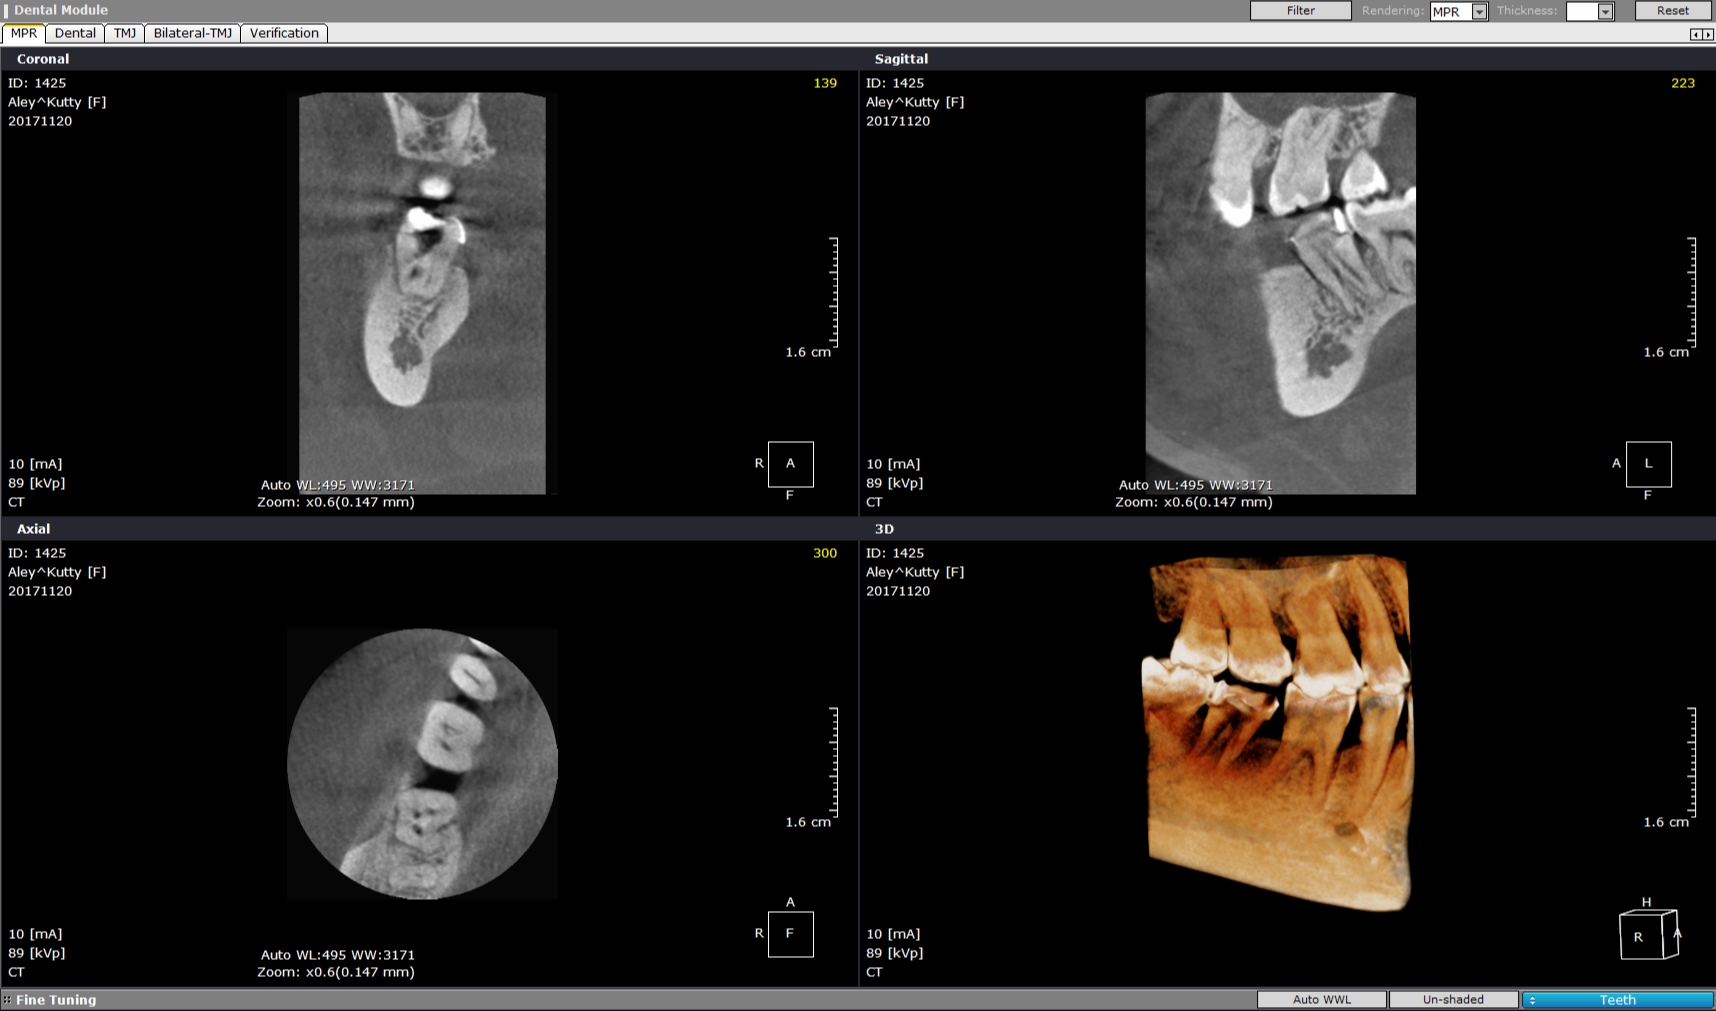

Pt 50 YOF presented with dislodged crown and severe pain in the recently RCT done #31. Started Re-treatment, after cleaning the chamber saw three orifices and finished the canals preparation, but was not sure of the distolinugal. I did not diagnose perforation as there was no bleeding nor patient complained of any pain during the preparation. Later Scan confirmed perforation and was sealed with fiber reinforced composite.